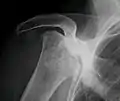

Radiography of total avascular necrosis of right humeral head. Woman of 81 years with diabetes of long evolution.